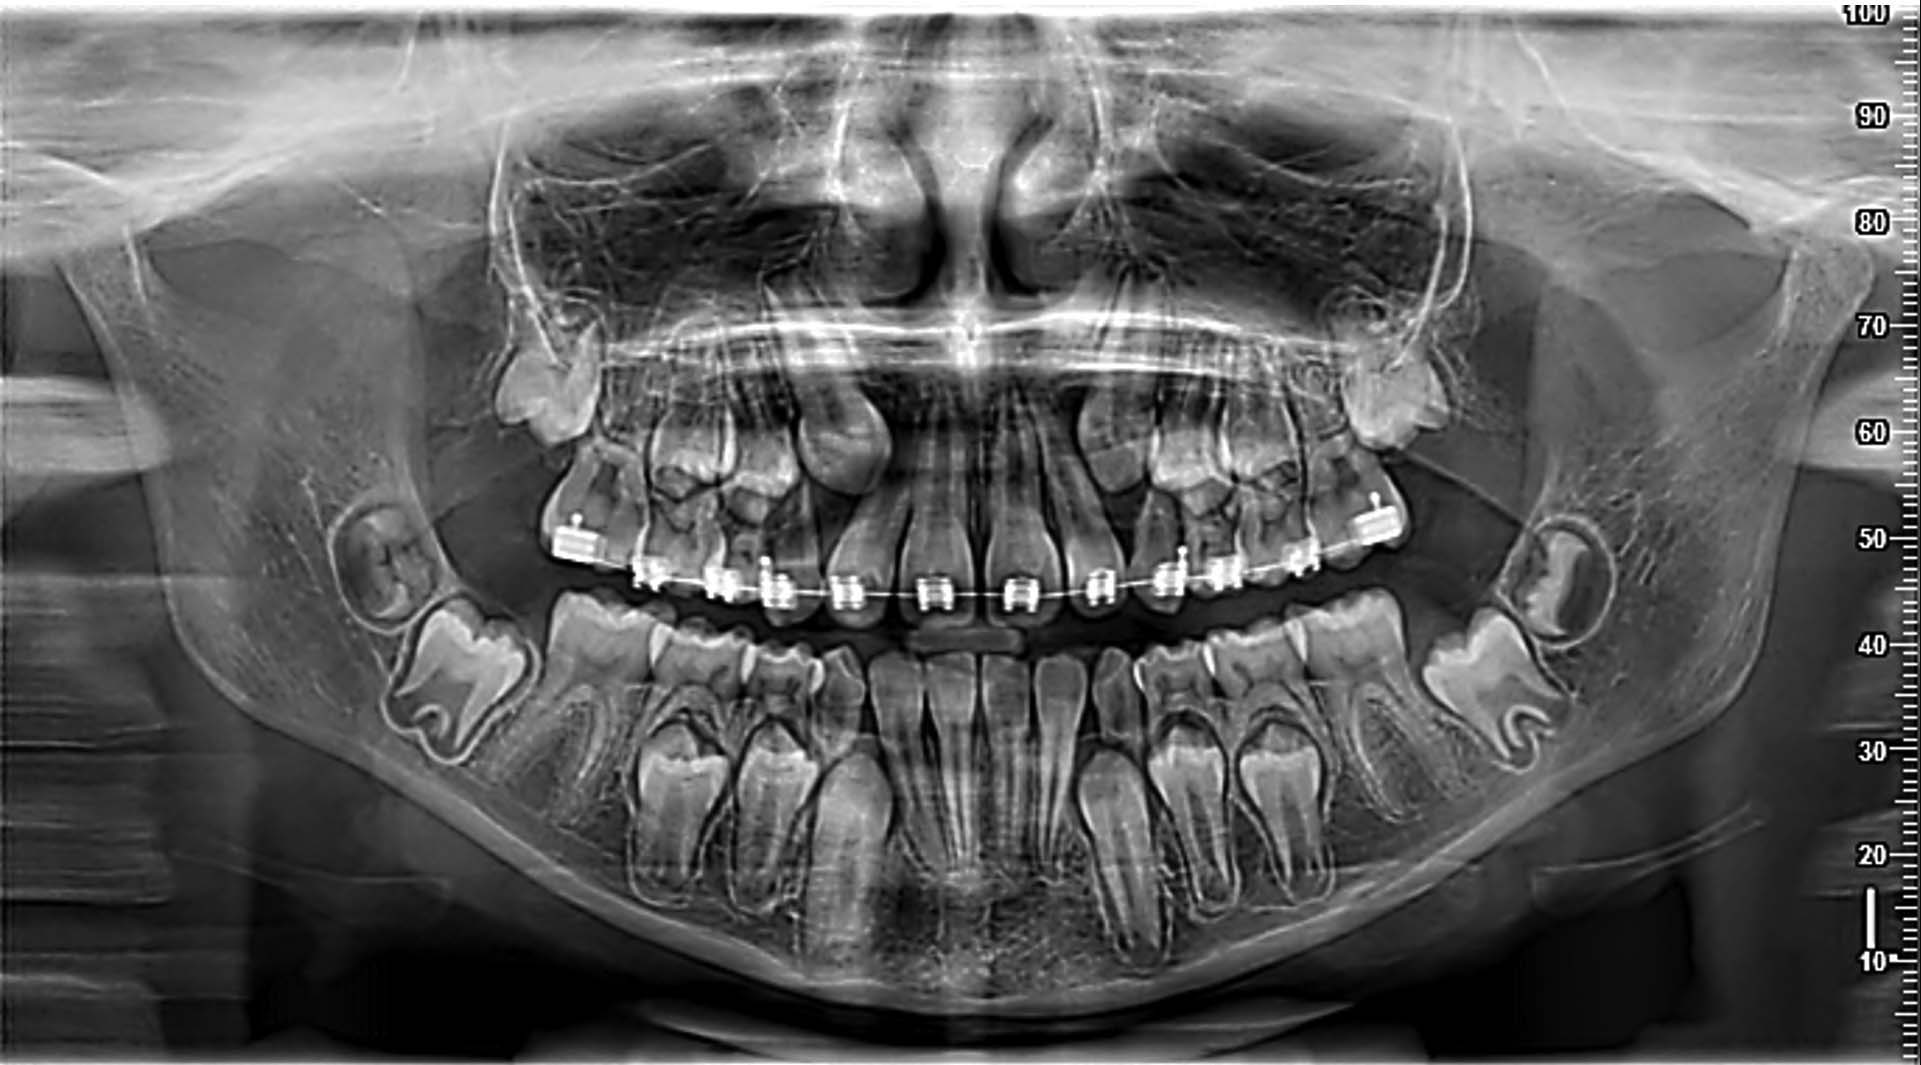

Yeni nesil hassas Cmos Flat Panel Teknolojisi. Görüntü kesitleri eskiye göre 2 kat daha keskin ve net görüntü almayı sağlamaktadır. Panoramik görüntülemede devrim yaratan Panoral 5 MultiPan çekim tekniği ile tek panoramik doz ile 5 ayrı katmanda görüntü alınır. Reel 16 bit yüksek gri skalası ile yüksek çözünürlük ve kesin tanı imkânı sunmaktadır. PANORAL 5 MULTIPAN Panoramik Röntgen Çekim Tekniği: CMOS Flat Panel Hassas Sensör teknolojisi tek bir panoramik doz ile horizontal düzlemde 3 mm. aralıkla, hastanın 5 ayrı vertikal panoramik görüntüsünün elde edilmesini sağlamaktadır. Bu şekilde net alan derinliğine girmeyen bir diş var ise bir önceki veya bir sonraki filmde görülebilir. Panoral 5 MULTIPAN görüntüleme tekniği; maloklüzyon ve hasta pozisyonlandırma hataları nedeniyle oluşabilecek görüntü bozukluklarını elemine edebilmektedir. Böylelikle panoramik röntgen çekimlerinde pozisyonlandırma hatalarına bağlı çekim tekrarlarına da gerek kalmaz.

PANORAMİK: Çene yapısının ve odak katmanının otomatik seçimi.

Endodontik değerlendirmeler için sadece ilgili bölgedeki ayrıntılı teşhisler yapılabilmektedir. 2D görüntülerden çok daha derinlemesine gömülü dişler arasındaki ilişkilerin neredeyse bir periapikal dozunda incelenmesi sağlar.